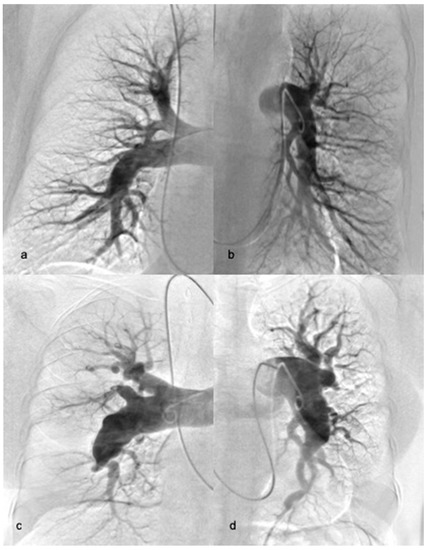

2.3. Balloon Pulmonary Angioplasty